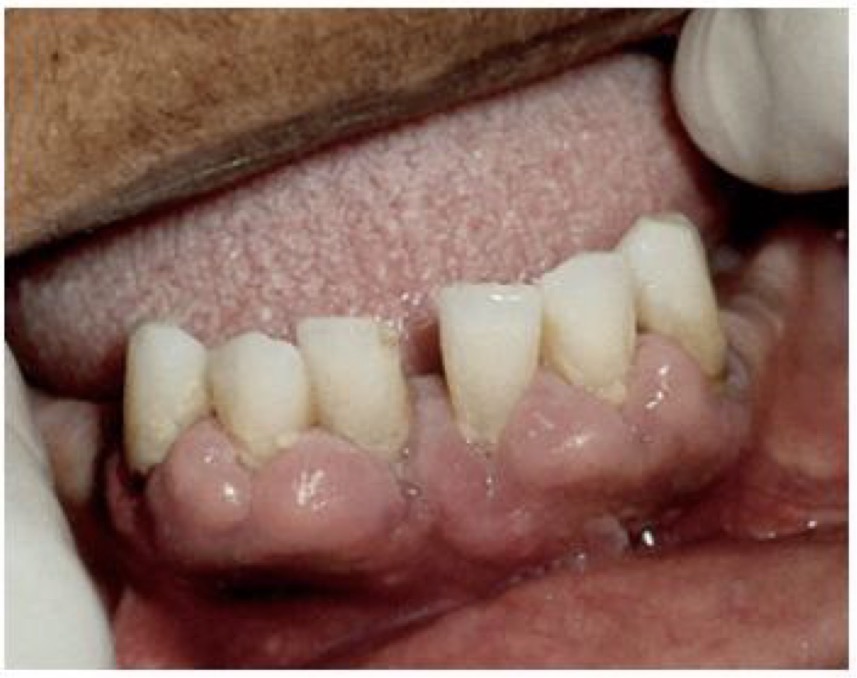

BN CÓ GAI NƯỚU TĂNG SINH, SƯNG TO, CẮNG BÓNG

SỜ DAI, KHÔNG ĐAU, KHÔNG CHẢY MÁU *

CHẨN ĐOÁN

TRIỂN DƯỠNG NƯỚU DO THUỐC PHENYTOIN

TRIỂN DƯỠNG NƯỚU DO DÙNG THUỐC PHENYTOIN

CHẨN ĐOÁN?